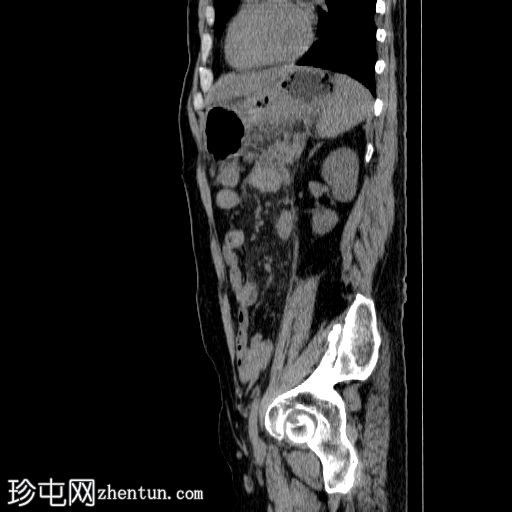

3.jpg

矢状面

非造影

胰体尾弥漫性增大,特征为胰腺实质低强化,无明显坏死区域。

病变范围如下:

病变横向延伸至左前肾旁间隙,伴有Gerota筋膜增厚。

病变向下延伸至盆腔。

在疾病早期,可能出现胰腺肿大、胰腺组织低增强、胰周脂肪条带、积液和筋膜增厚。